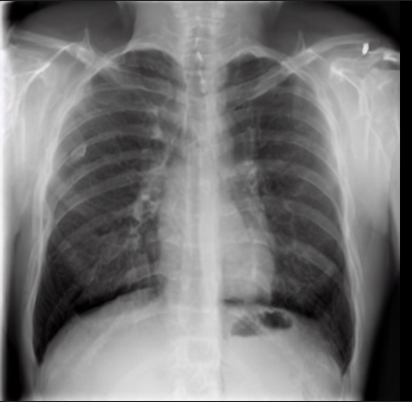

4.1 Qualitative Evaluation of Healthy Counterpart Generation

Example images from the disease COVID-19 Radiography Database and their generative healthy counterparts are given in figure 2. The images on the far left are instances of the lung opacity class from the real images in the dataset. The images in the middle column are examples of the generated healthy counterfactuals obtained via latent space diffusion, with RadBERT-guided textual-conditioning via a conditional prompt “normal chest x-ray”. A total of 75 diffusion inference steps are used with image conditioning strength=0.85 and guidance scale=7.5. (The former indicates the level of constraint on changes to the original input image and the latter is the weight given to the textual encoder conditioning in the generation of the image, ranging over [0,1] and [0,9], respectively).

Side-by-side inspection of the generated healthy counterfactuals (as per fig. 2) suggests that, as required, only minimal perturbation is made to the original image with respect to healthy pixels -i.e. localized image sites without structural medical defects. (In the top row, the medical structural defect in the original image is due to a lung opacity, and characterized via a relatively complex interaction between the imaging modality and subject manifesting as ‘gaps’ in the corresponding portions of the lung scan). The healthy/non-healthy discrepancy maps in all of these cases are obtained via masked subtraction of the original image from the generated image (the ground truth segmentation masks correspond to the broad area of interest –i.e. the complete lung). The generated healthy tissue is thus a subset of the mask and is shown in the final column of fig. 2 for the respective cases.